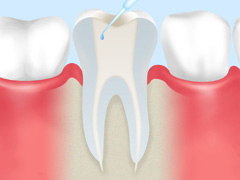

マイクロスコープを使った精密治療の流れの参考として、根管治療における治療ステップをご紹介します。

①:除去・洗浄

マイクロスコープを使った拡大視野下で、虫歯に汚染されている組織(神経・血管・歯質)をしっかり除去・洗浄します。